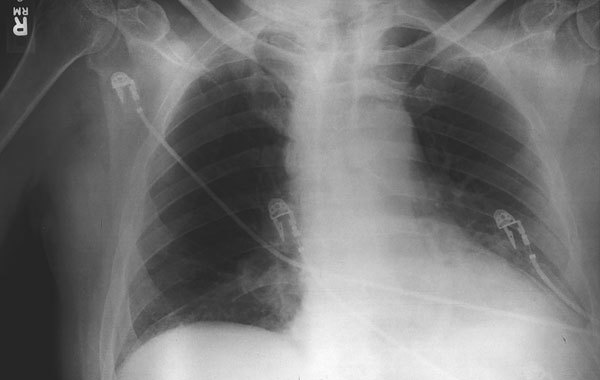

Large Gram- positive rods are observed on a blood smear from a 60-year –old patient with a severe flu-like illness accompanied by the chest X-ray as below. The virulence of this organism is associated with its capacity to survive in the blood stream and to the production of two toxins, one of which is a/an

Answer: adenylate cyclase

Explanation: This is a likely case of pulmonary anthrax. The main clues here are the widening of the mediastinum on Xray (think inhalational anthrax) supported by the fact that the disease is severe and the organism can survive in the blood stream. The causative agent of anthrax, Bacillus anthracis makes two toxins: lethal toxin and edema toxin (an adenylate cyclase).